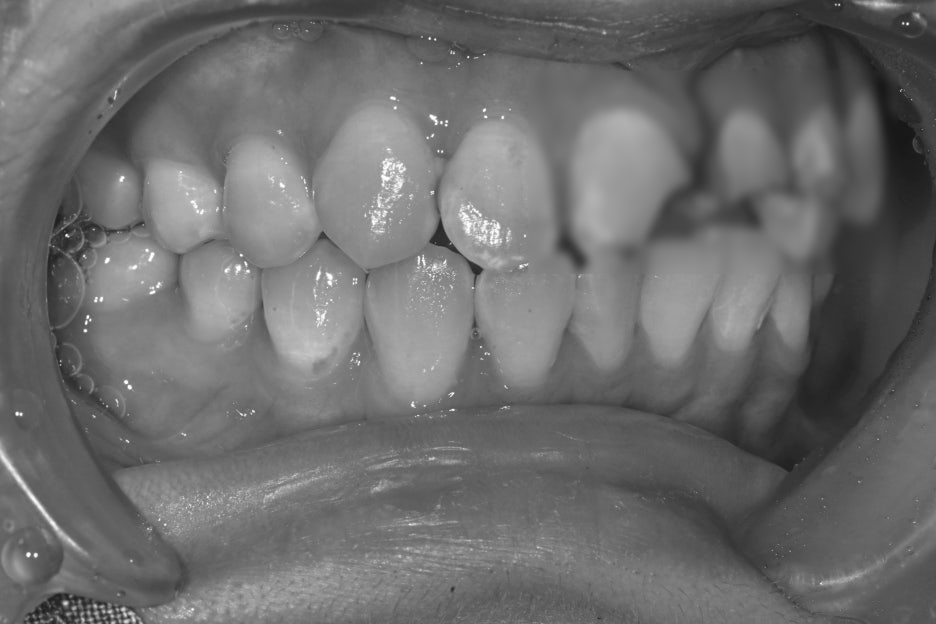

Before and after treatment photos

Photos before and after treatment

After treatment, the patient said,

“Now my front teeth are aligned again, so I feel more confident when smiling,”

and expressed satisfaction.

She also felt more reassured because people around her said it looked natural.